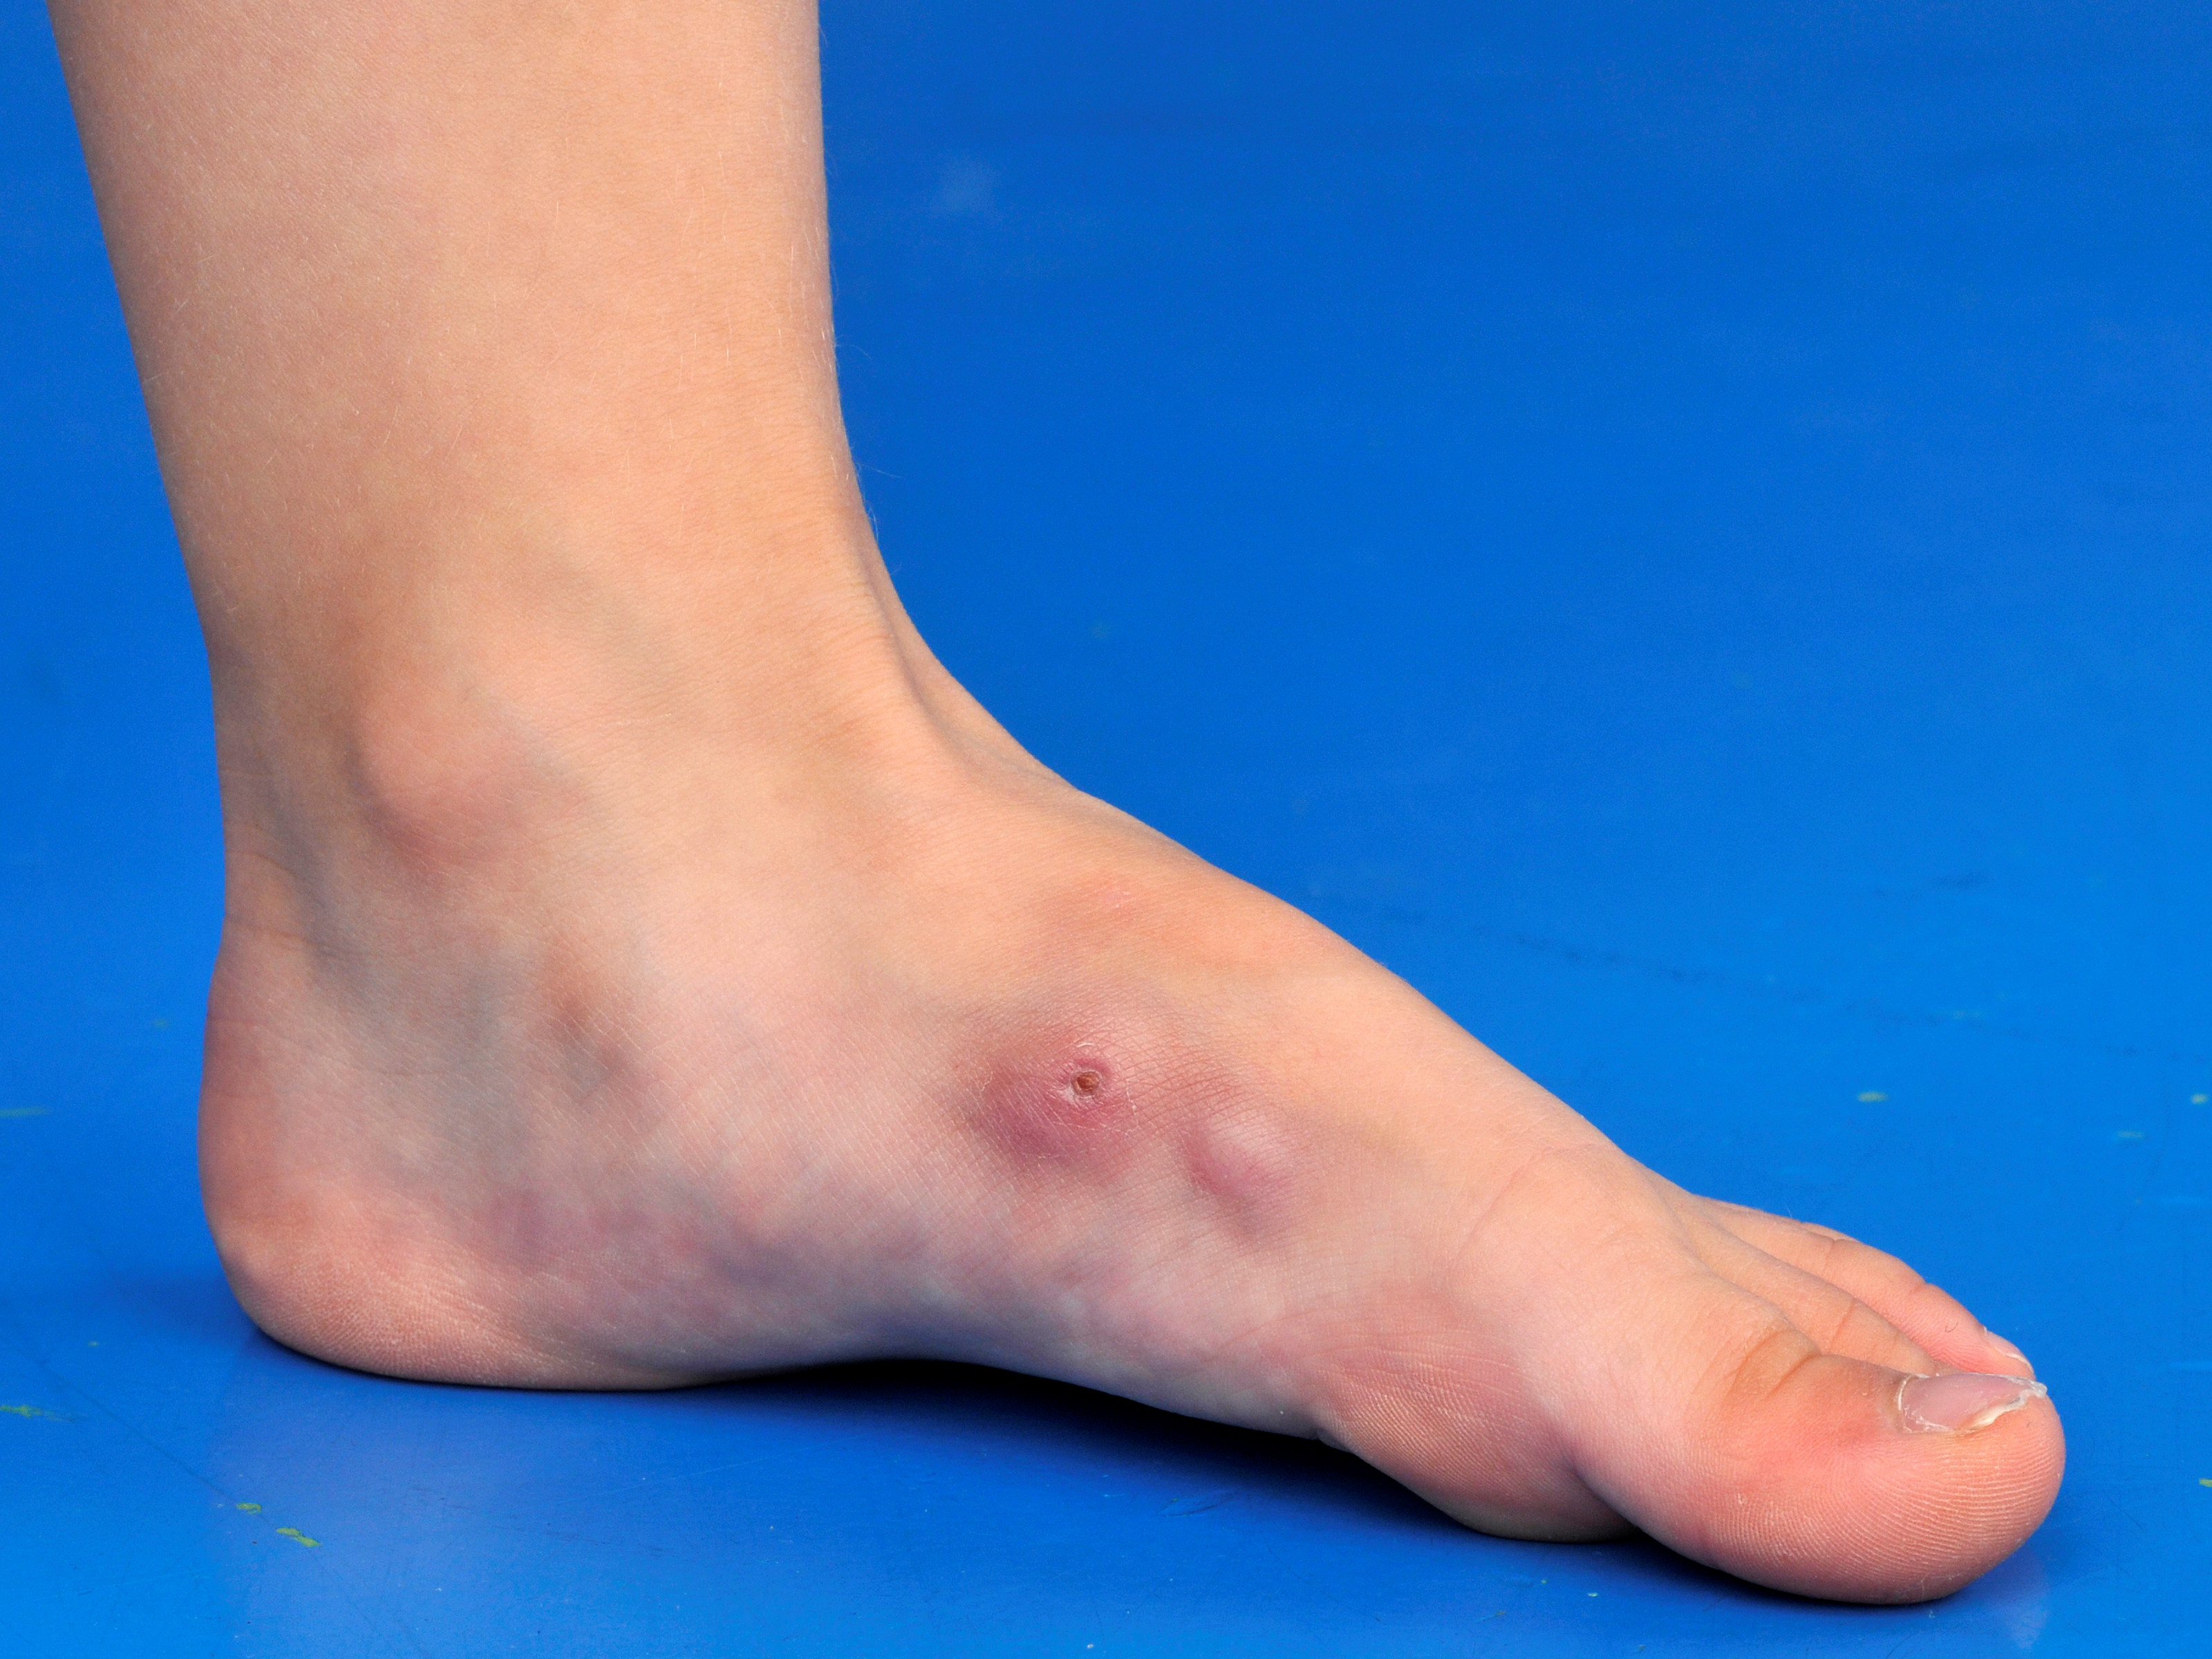

Klinisch beeld:

Solitaire langzaam groeiende vast aanvoelende tumor, huidkleurig, paars of lichtbruin. Kan exofytisch groeien, of de diepte in, lijkend op een dermatofibroom. Er bestaan ook plaque-vormen, multinodulaire vormen, morfea-achtige sclerotische plaques, en gepigmenteerde varianten (Bednar tumor, vooral bij de gepigmenteerde huid). Ulceratie en bloeding kunnen voorkomen in latere stadia. De laesies kunnen centimeters groot worden en groeien ook de diepte in. Dermatofibrosarcoma protuberans ontstaat vooral op de romp, gevolgd door de extremiteiten. Bij circa 10-15% presenteert het zich in het hoofd hals gebied.

DD: dermatofibroom, keloid, hypertrofisch litteken, epidermale cyste, leiomyosarcoom, andere weke delen tumor, amelanotisch melanoom, Merkelcel carcinoom, metastase van een tumor in de huid, morfea.